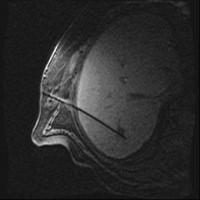

Under local anesthesia and administration of pain medication, the tumor is punctured under computer tomographic (CT), magnetic resonance imaging view with subsequent insertion of the catheters into the target volume.

Images: Brachytherapy for liver metastases: first MRI-guided placement of one catheter per tumor followed by irradiation through the catheters using Iridium 192 radiation source.